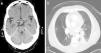

Cranial computed axial tomography (CT) revealed a 1cm suprasellar nodular lesion with well-defined borders in the upper part of the pituitary stalk, with moderate contrast enhancement (Fig. 1a). The first possibility raised was that it was in the pituitary stalk, infundibulum or adjacent meningeal structures. Brain magnetic resonance imaging (MRI) showed a 1cm suprasellar nodule, attached to the pituitary stalk that affected the hypothalamus and optic chiasm, consistent with an adenoma. There were no findings of interest on the magnetic resonance angiography of the circle of Willis. A 1.5cm×1cm×1.8cm mass was observed on the pituitary gland MRI, affecting the pituitary stalk and the hypothalamic region, consistent with metastasis. Bone scintigraphy was normal. The patient was discharged from neurology and followed-up in outpatients. Three months later, he was readmitted due to fever and bloody sputum, for which he was referred to Respiratory Medicine.

The chest X-ray did not show any significant changes with respect to the previous one. On the chest–abdominal–pelvic CT scan, a soft tissue density infiltrative lesion was noted which surrounded the left hilum and extended to the basal pyramid, with a slight decrease in volume in the left lower lobe and bilateral pleural effusion (Fig. 1b). Bronchoscopy revealed a tumour in the left sixth segment; the biopsy was consistent with undifferentiated small cell carcinoma. Spirometry showed a severe obstructive disorder, with a negative bronchodilator test. With the diagnosis of pituitary metastasis with hypopituitarism secondary to undifferentiated small cell carcinoma (stage IV), the patient began chemotherapy. He remained stable and tumour size was reduced in the first six months. However, he died one year later due to disease progression.